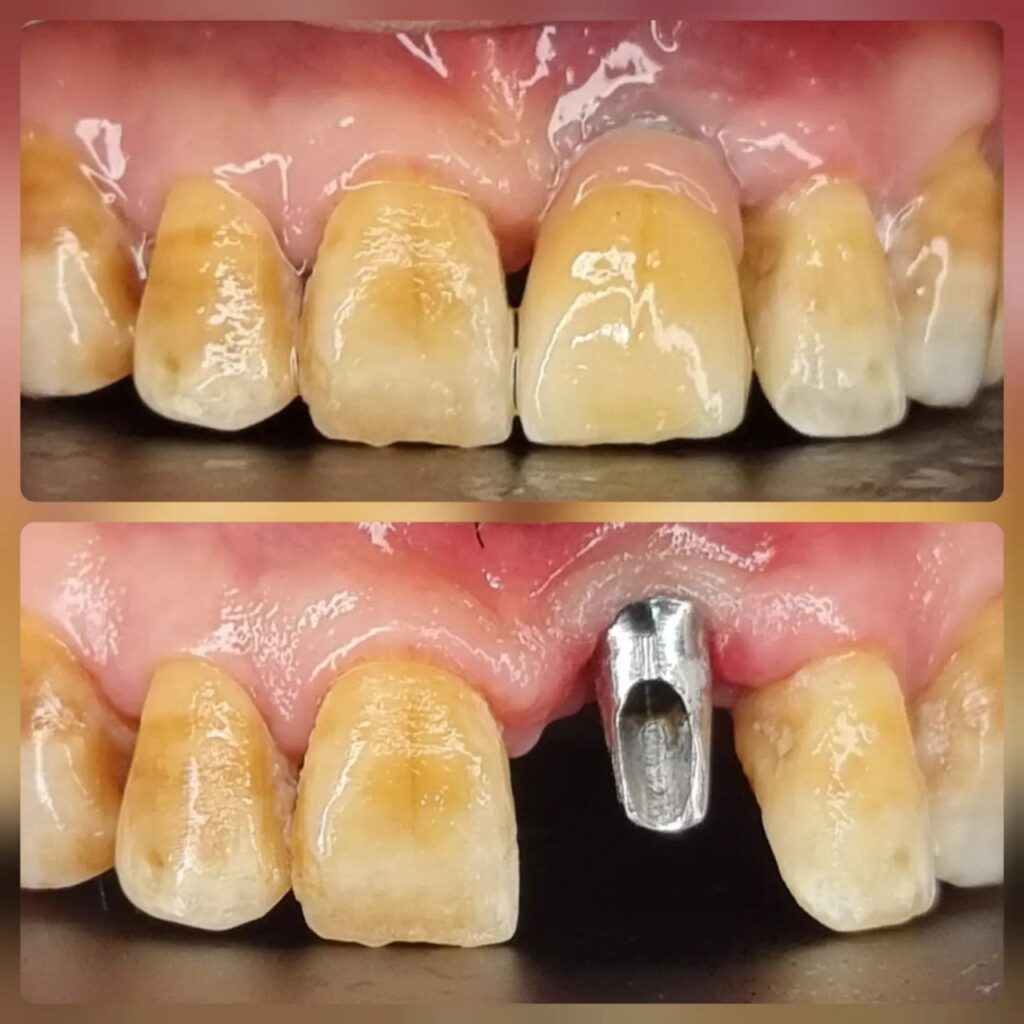

کاشت ایمپلنت دندان

اطمینان حاصل کردن از اینکه دندانهایتان به نحوی زیبا و طبیعی جایگزین شدهاند، از اهمیت بسیاری برخوردار است. ایمپلنت دندان به عنوان یک روش درمانی دائمی در دندانپزشکی شناخته میشود که حاصل آن، یک دندان زیبا و طبیعی در دهان شما خواهد بود.

هرچند که این روش درمانی هزینهی بیشتری نسبت به روشهای دیگر دارد، اما ارزش زیبایی که ایجاد میکند، قابل انکار نیست. ایمپلنتها به قدری شبیه به دندانهای طبیعی هستند که به سختی میتوان آنها را از دیگر دندانها تشخیص داد.